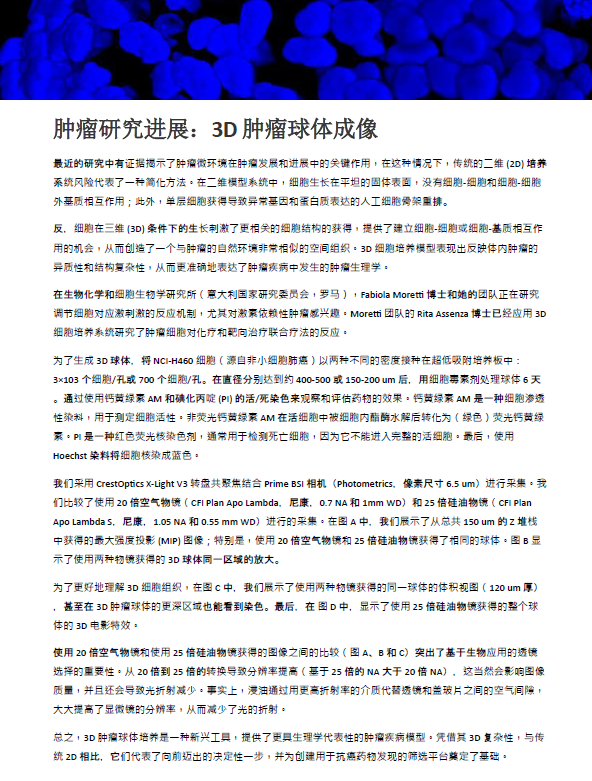

我们采用 CrestOptics X-Light V3 转盘共聚焦结合 Prime BSI 相机(Photometrics,像素尺寸 6.5 um)进行采集。我们比较了使用 20 倍空气物镜(CFI Plan Apo Lambda,尼康,0.7 NA 和 1mm WD)和 25 倍硅油物镜(CFI Plan Apo Lambda S,尼康,1.05 NA 和 0.55 mm WD)进行的采集。在图 A 中,我们展示了从总共 150 um 的 Z 堆栈中获得的最大强度投影 (MIP) 图像;特别是,使用 20 倍空气物镜和 25 倍硅油物镜获得了相同的球体。图 B 显示了使用两种物镜获得的 3D 球体同一区域的放大。

为了更好地理解 3D 细胞组织,在图 C 中,我们展示了使用两种物镜获得的同一球体的体积视图(120 um 厚),甚至在 3D 肿瘤球体的更深区域也能看到染色。最后,在 图 D 中,显示了使用 25 倍硅油物镜获得的整个球体的 3D 电影特效。

图 C:使用 20 倍空气物镜(左)和 25 倍硅油物镜(右)获得的球体的 3D 体积视图。活细胞用钙黄绿素(绿色)标记,死细胞用 PI(红色)标记。细胞核用 Hoechst(蓝色)染色。沿 Z 轴的比例尺:120 um。这些图像是使用 CrestOptics X-Light V3 转盘获取的。